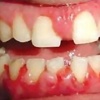

ANUG (äge nekrotiseeruv haavandiline gingiviit/parodontiit)

ANUG' ist tingitud igemete punetus, turse ja errosioon

Kliiniline pilt:

- Valkjas-kollakas–hallikas katt igeme serval (pseudomembraanid)

- Interdentaalsete papillide nekroos

- Märkimisväärne igemete veritsemine (palju rohkem kui gingiviidi või parodontiidi korral)

- Väga valusad igemed